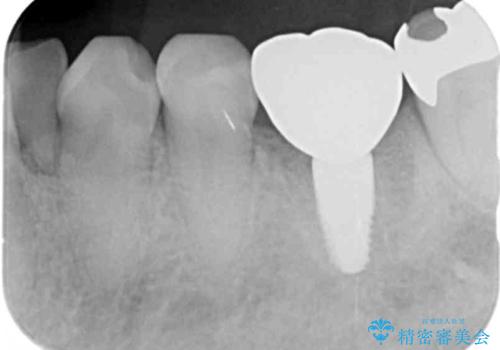

X線写真より問題のなかった根管治療は行わず、クラウンを除去し仮歯でを装着したのちジルコニアクラウンを製作していきます。

失活歯の治療について

神経をすでに取られている歯の治療を行う場合、コアを除去したのちの再根管治療を行う場合とクラウンのみやり替えする場合、状況に応じて適切な治療をご提案いたします。